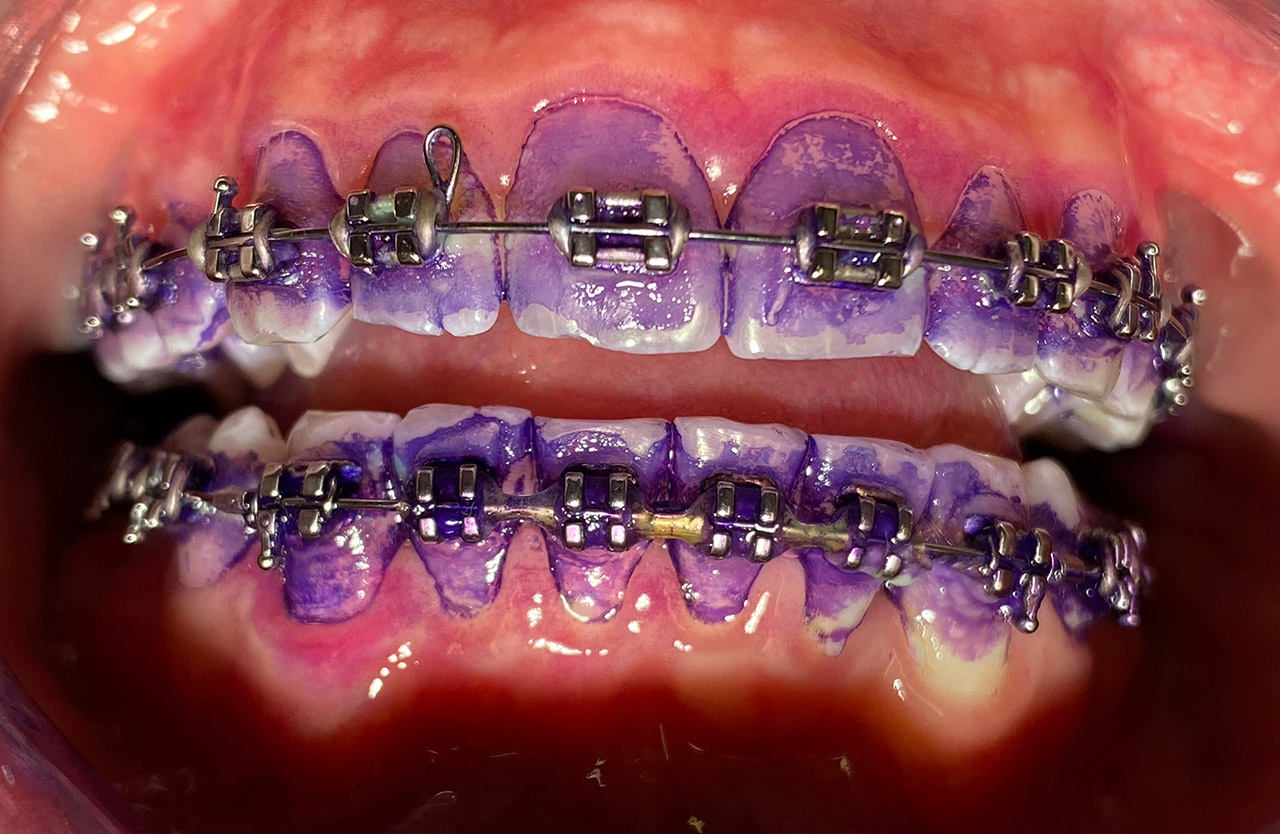

Prophylaxe/professionelle Zahnreinigung:

Zur Motivation, Information und Instruktion einfärben der Beläge (bakterieller Biofilm) bei jungem Patienten in kieferorthopädischer Behandlung.

Reinigung der Zähne mit Pulverstrahltechnik minimalinvasiv und zahnschonend und wo noch nötig gezielt mit Ultraschall.